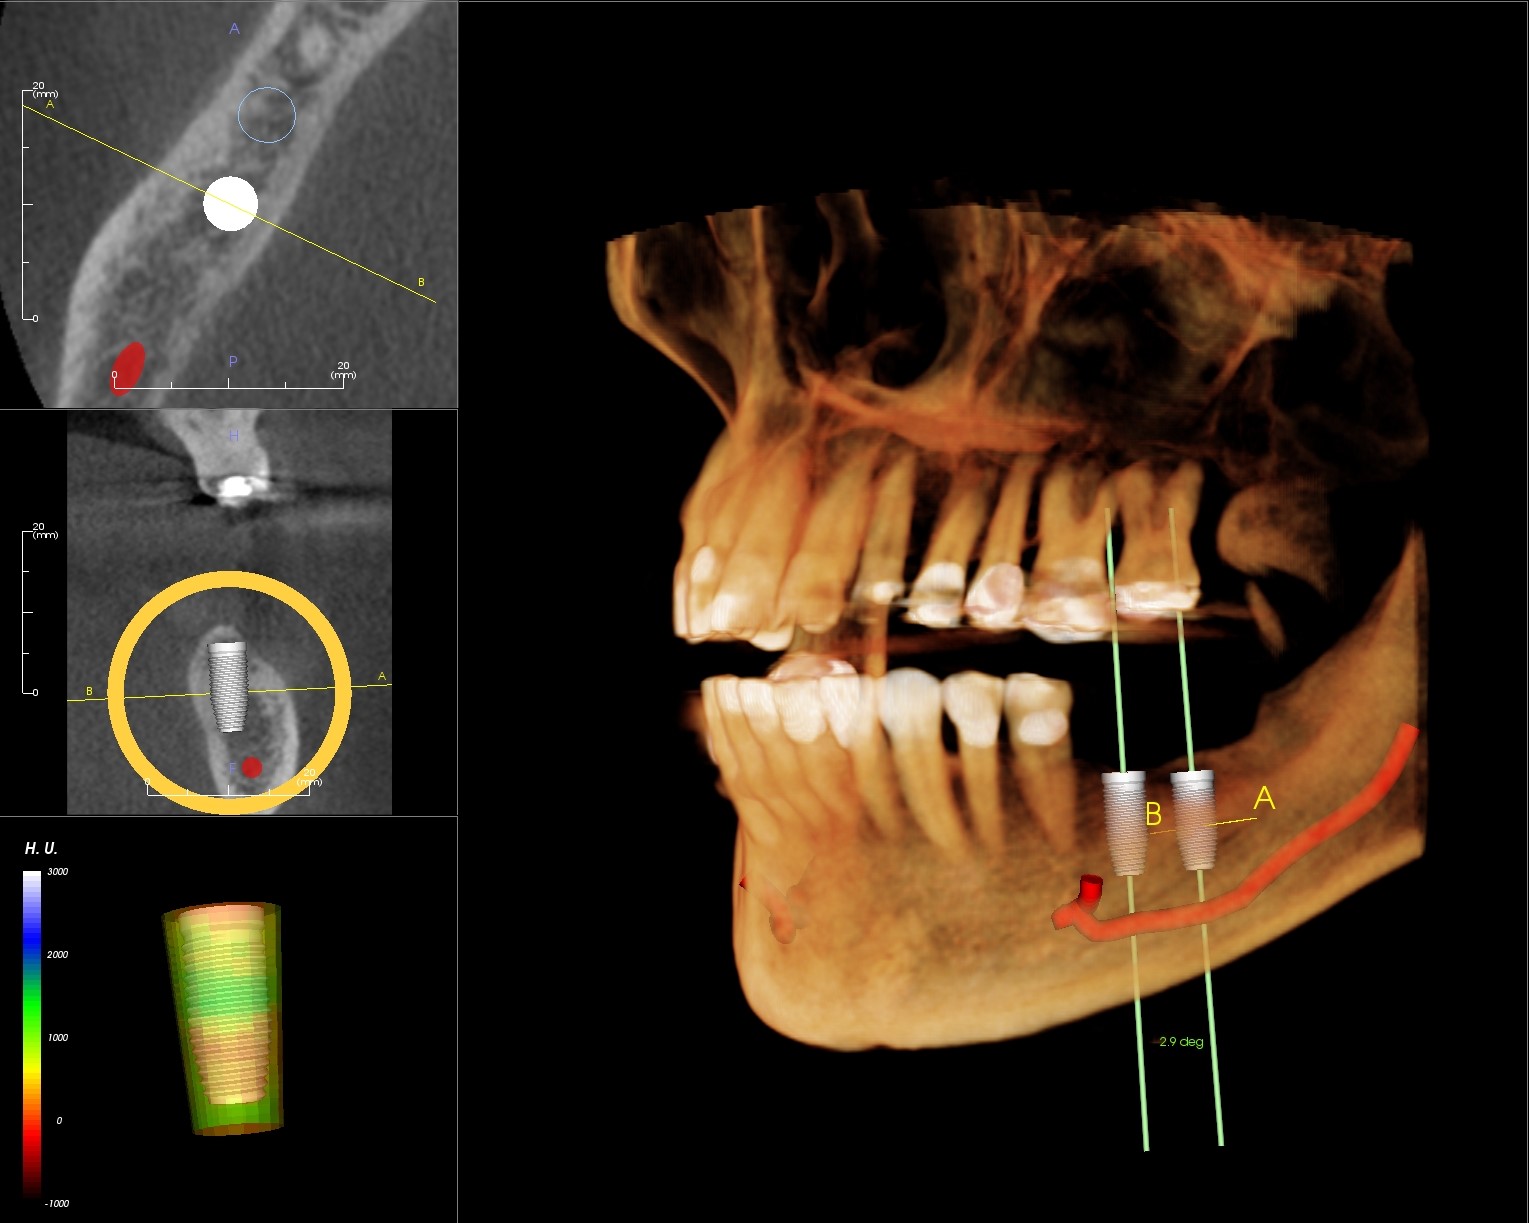

From www.facialart.com

Loose Dental Implant? How to Differentiate Between Bone Loss from Dental X Ray Bone Loss If you note the bone between the mandibular second and third molar. If you have significant bone loss, your dentist can use regenerative bone grafting to supplement the bone surrounding your teeth. Reveal changes in the bone or in the root canal resulting from infection. Your dentist may assign a stage and a. In addition, several other signs may alert. Dental X Ray Bone Loss.